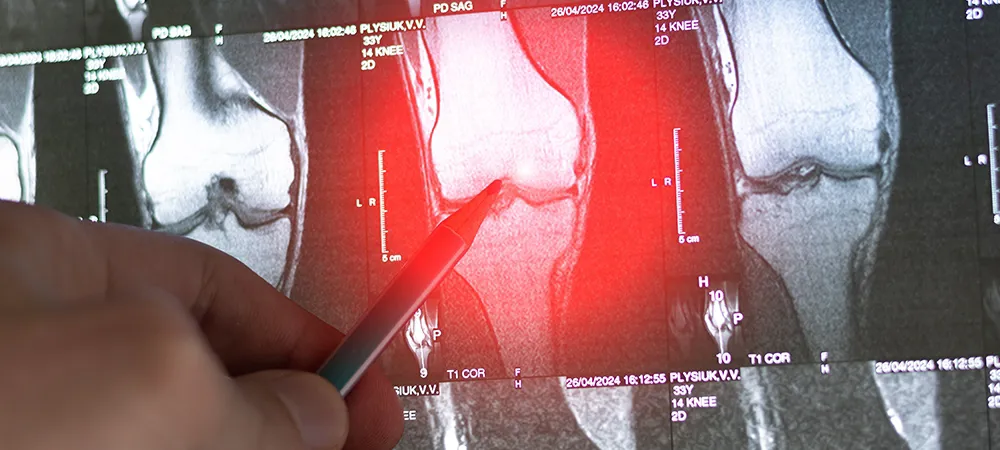

Doktor, tümörü daha ayrıntılı olarak tanımlamak için bilgisayarlı tomografi (BT) veya manyetik rezonans görüntüleme (MRG) taramaları da isteyebilir. Bu taramalar, özellikle yumuşak dokular (kaslar, tendonlar, sinirler ve kan damarları dahil) ve tümörün kıkırdak kısmı olmak üzere, röntgenlerden daha fazla ayrıntı sağlayabilir.

Tümörün yüzeyindeki kıkırdağı incelemek için MR taraması kullanılabilir. Osteokondromun kanserli bir tümöre dönüşmesi nadir olsa da mümkündür. Yetişkinlerde, tümörün üzerinde kalın bir kıkırdak tabakası, böyle bir değişimin belirtilerinden biridir. Yetişkin bir hastada tümör büyüyorsa veya ağrılı hale gelmişse, kanser açısından kontrol edilmelidir.